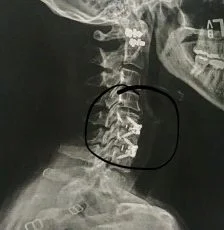

My Anterior Cervical Spine Surgery Changed My Life